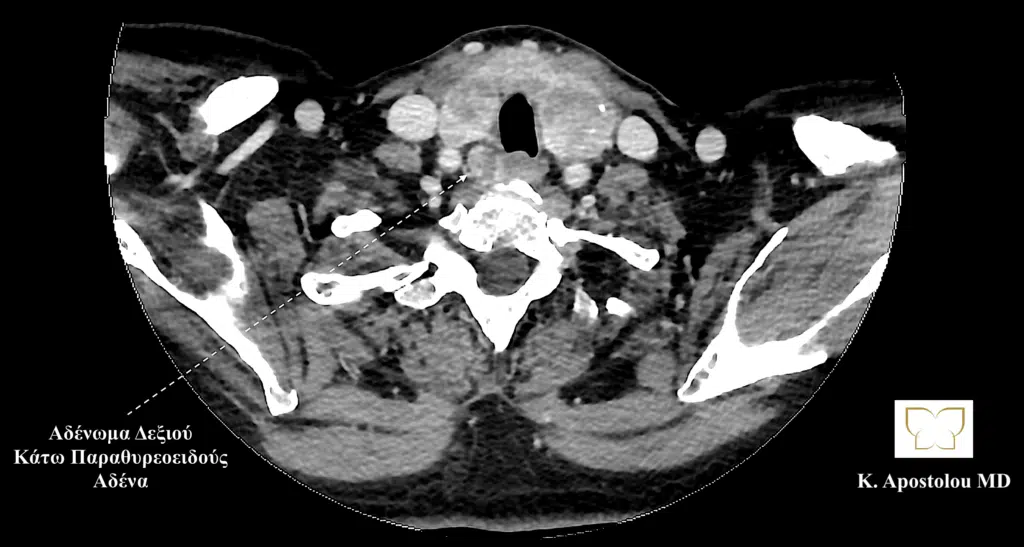

Ομοίως, η αξονική τομογραφία αποκάλυψε την παρουσία τριών αδενωμάτων παραθυρεοειδούς και πιο συγκεκριμένα του δεξιού άνω παραθυρεοειδούς, του αριστερού άνω παραθυρεοειδούς και του δεξιού κάτω παραθυρεοειδούς αδένα, καθώς και την παρουσία διόγκωσης του θυρεοειδούς αδένα με κατάδυση αυτού στο ανώτερο μεσοθωράκιο και την παρουσία πολλαπλών όζων θυρεοειδούς (καταδυόμενη πολυοζώδης βρογχοκήλη).

αδενωμα δεξιου κατω παραθυρεοειδους